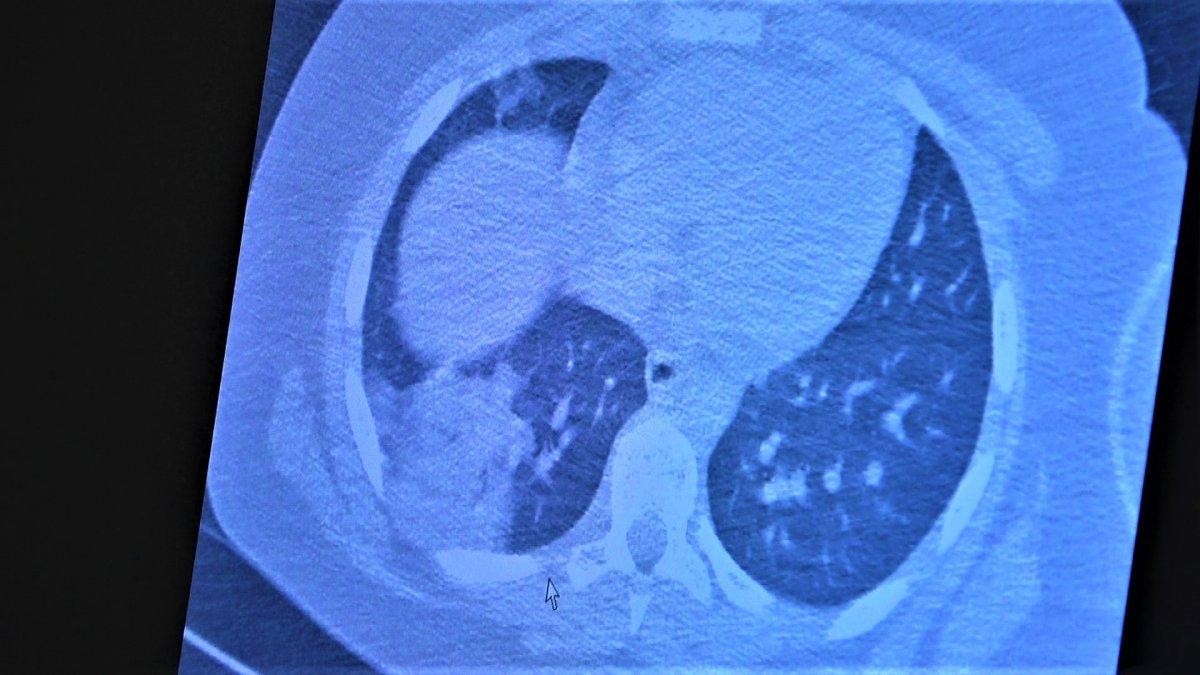

Çocukların akciğer tomografilerini inceleyen Özkaya, açıklamalarına şu ifadeler ile devam etti:

“11 yaşında kovid pozitif bir öğrencimiz, yüksek ateş ve nefes darlığı ile bize geldi. Ciddi akciğer tutulumu var. Geçen yıl ‘bu çocuklar hastalıktan etkilenmiyor’ diyorduk. Bu çocukta görüyorsunuz buzlu camlar ve konsolidasyon alanlarla seyrediyor. Geçen yıl bu şekilde çok çocuk görmüyorduk. Önümüzdeki aylarda bu şekilde devam ederse çocuklarımızı kaybetmeye bile başlayabiliriz.